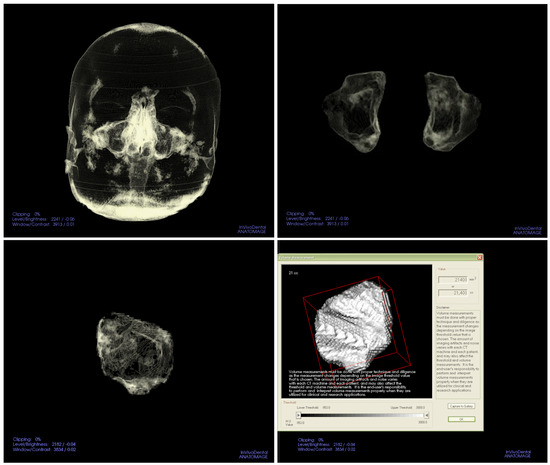

2. Materials and Methods